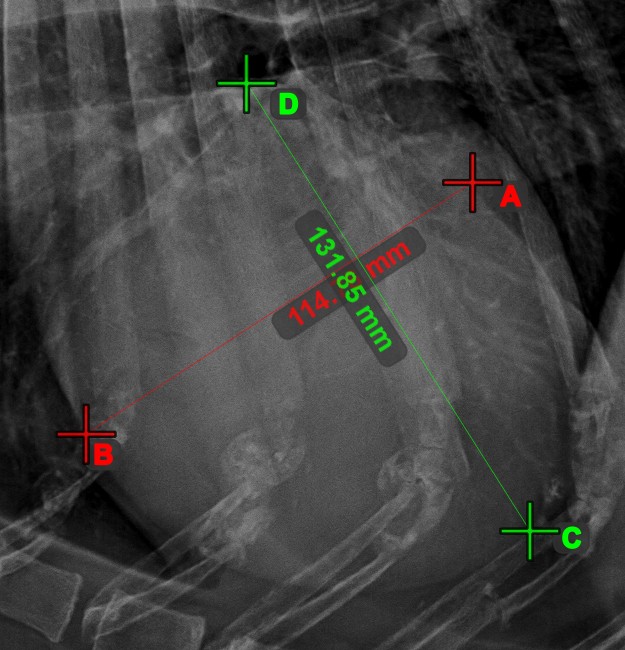

Line Intersection

Quickly and accurately locate and mark the intersection point between two existing lines by using the Line Intersection tool.

Select the tool from the left toolbar and assign it to one of the available mouse buttons. Select two lines that have already been drawn on the scene to complete the measurement. The intersection point of the line will be automatically calculated and marked on the scene. The intersection point of two lines will always be marked with the letter X.

Information

If two lines do not intersect directly, the intersection point of their extended projections on the scene will be marked.

../_images/image408.jpg ../_images/image37.jpg